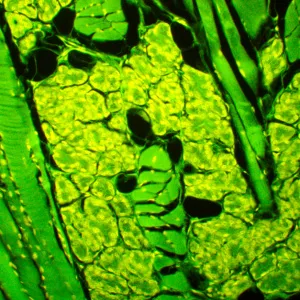

Микроскоп MAGUS Lum 450L – это модель, на которой можно проводить исследования как в светлом поле, так и в свете люминесценции, а при доукомплектовании микроскопа дополнительными компонентами станут доступны и исследования по темному полю, фазовому контрасту или в поляризованном свете. При исследованиях в свете люминесценции MAGUS Lum 450L освещает препарат синим или зеленым цветом – объекты, соответственно, производят зелено-желтый или красный свет. Люминесцентные микроскопы применяются в медицинских экспертизах, криминалистических или фармакологических исследованиях, в работе ветеринарного контроля и санэпиднадзора. Эта модель оснащена системой «умного» освещения, подстраивающей интенсивность света под характеристики объектива, и ЖК-экраном, на котором можно контролировать параметры работы.

- Для работы в свете люминесценции препарат освещается синим или зеленым светом и производит желто-зеленый или красный